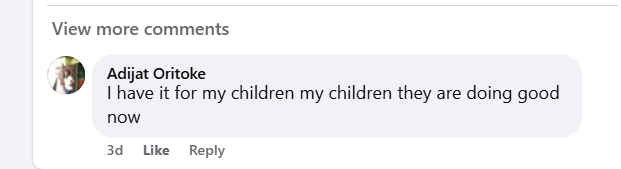

Understanding the Cause: Stress, aging, poor nutrition, and lack of mental stimulation are just a few factors contributing to cognitive decline. Over time, these elements can lead to more serious conditions like dementia and seizures, robbing individuals of their independence and vitality.

Reduced Risk of Dementia and Seizures: Protect your brain health for the long term. By addressing underlying issues, our Brain Booster products help reduce the risk of serious conditions like dementia and seizures.